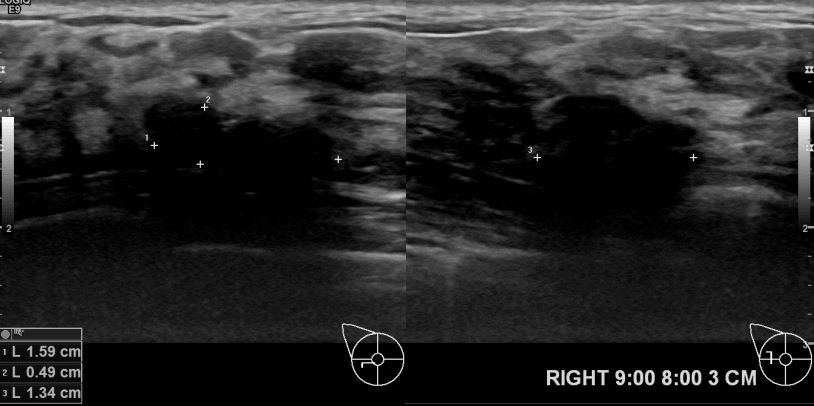

외부검사상 이상소견으로  조직검사 권유받아 내원하신 60대 여성분으로 우측 유방의 의심스러운혹 조직검사후 유방암 진단 되었읍니다